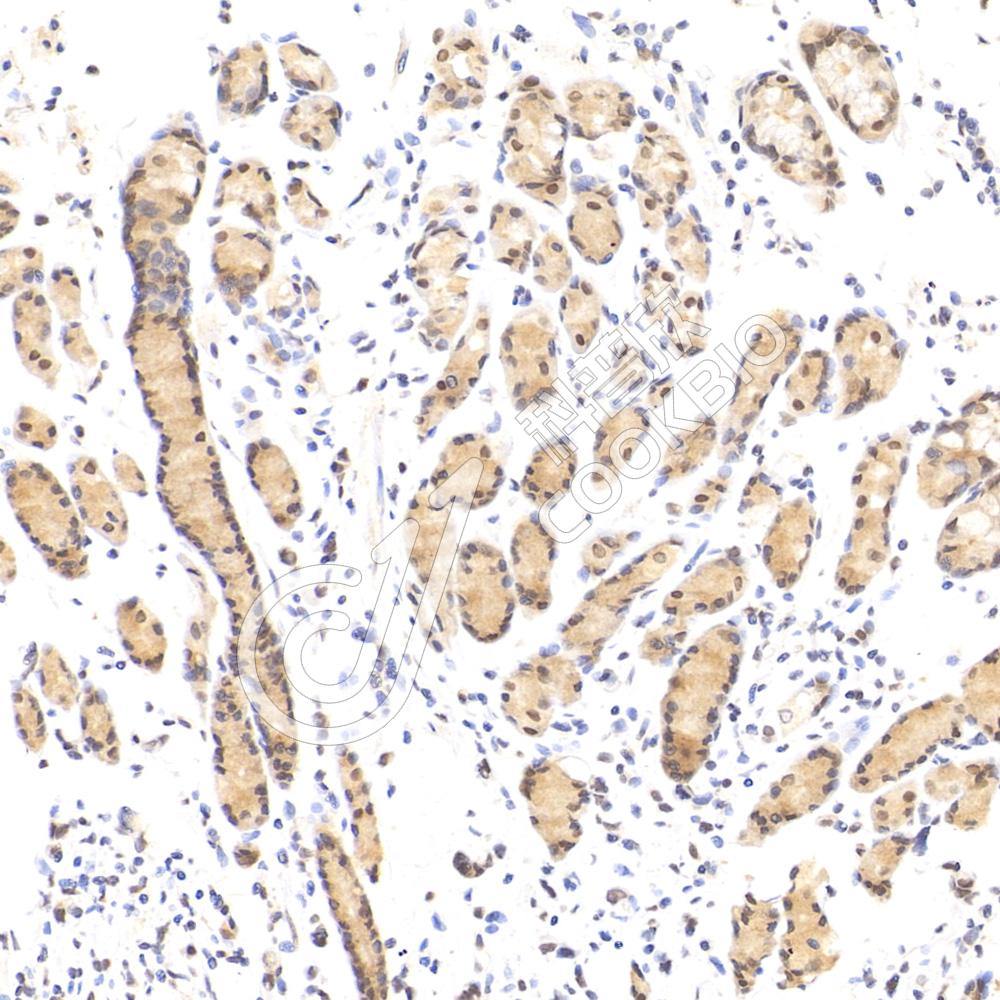

IHC检测PYK2蛋白(货号 K135487).

样品: 小鼠结肠, 4%多聚甲醛 (货号KSG1101) 固定12-24小时.

抗原修复: 柠檬酸抗原修复液(干粉, pH 6.0) (KSG1201), 98℃, 20分钟.

—抗: 1: 1700稀释, 4℃ 孵育过夜.

二抗: S-vision免疫组化多聚二抗(山羊抗兔),即用型 (货号KB3906), 室温孵育20分钟.